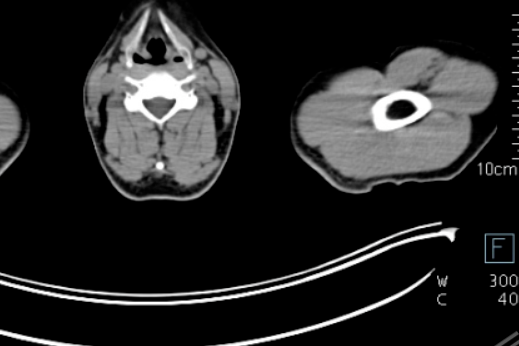

淋巴瘤治疗显成效!PET/CT 见证病灶「大撤退」

淋巴瘤治疗显成效!PET/CT 见证病灶 「大撤退」